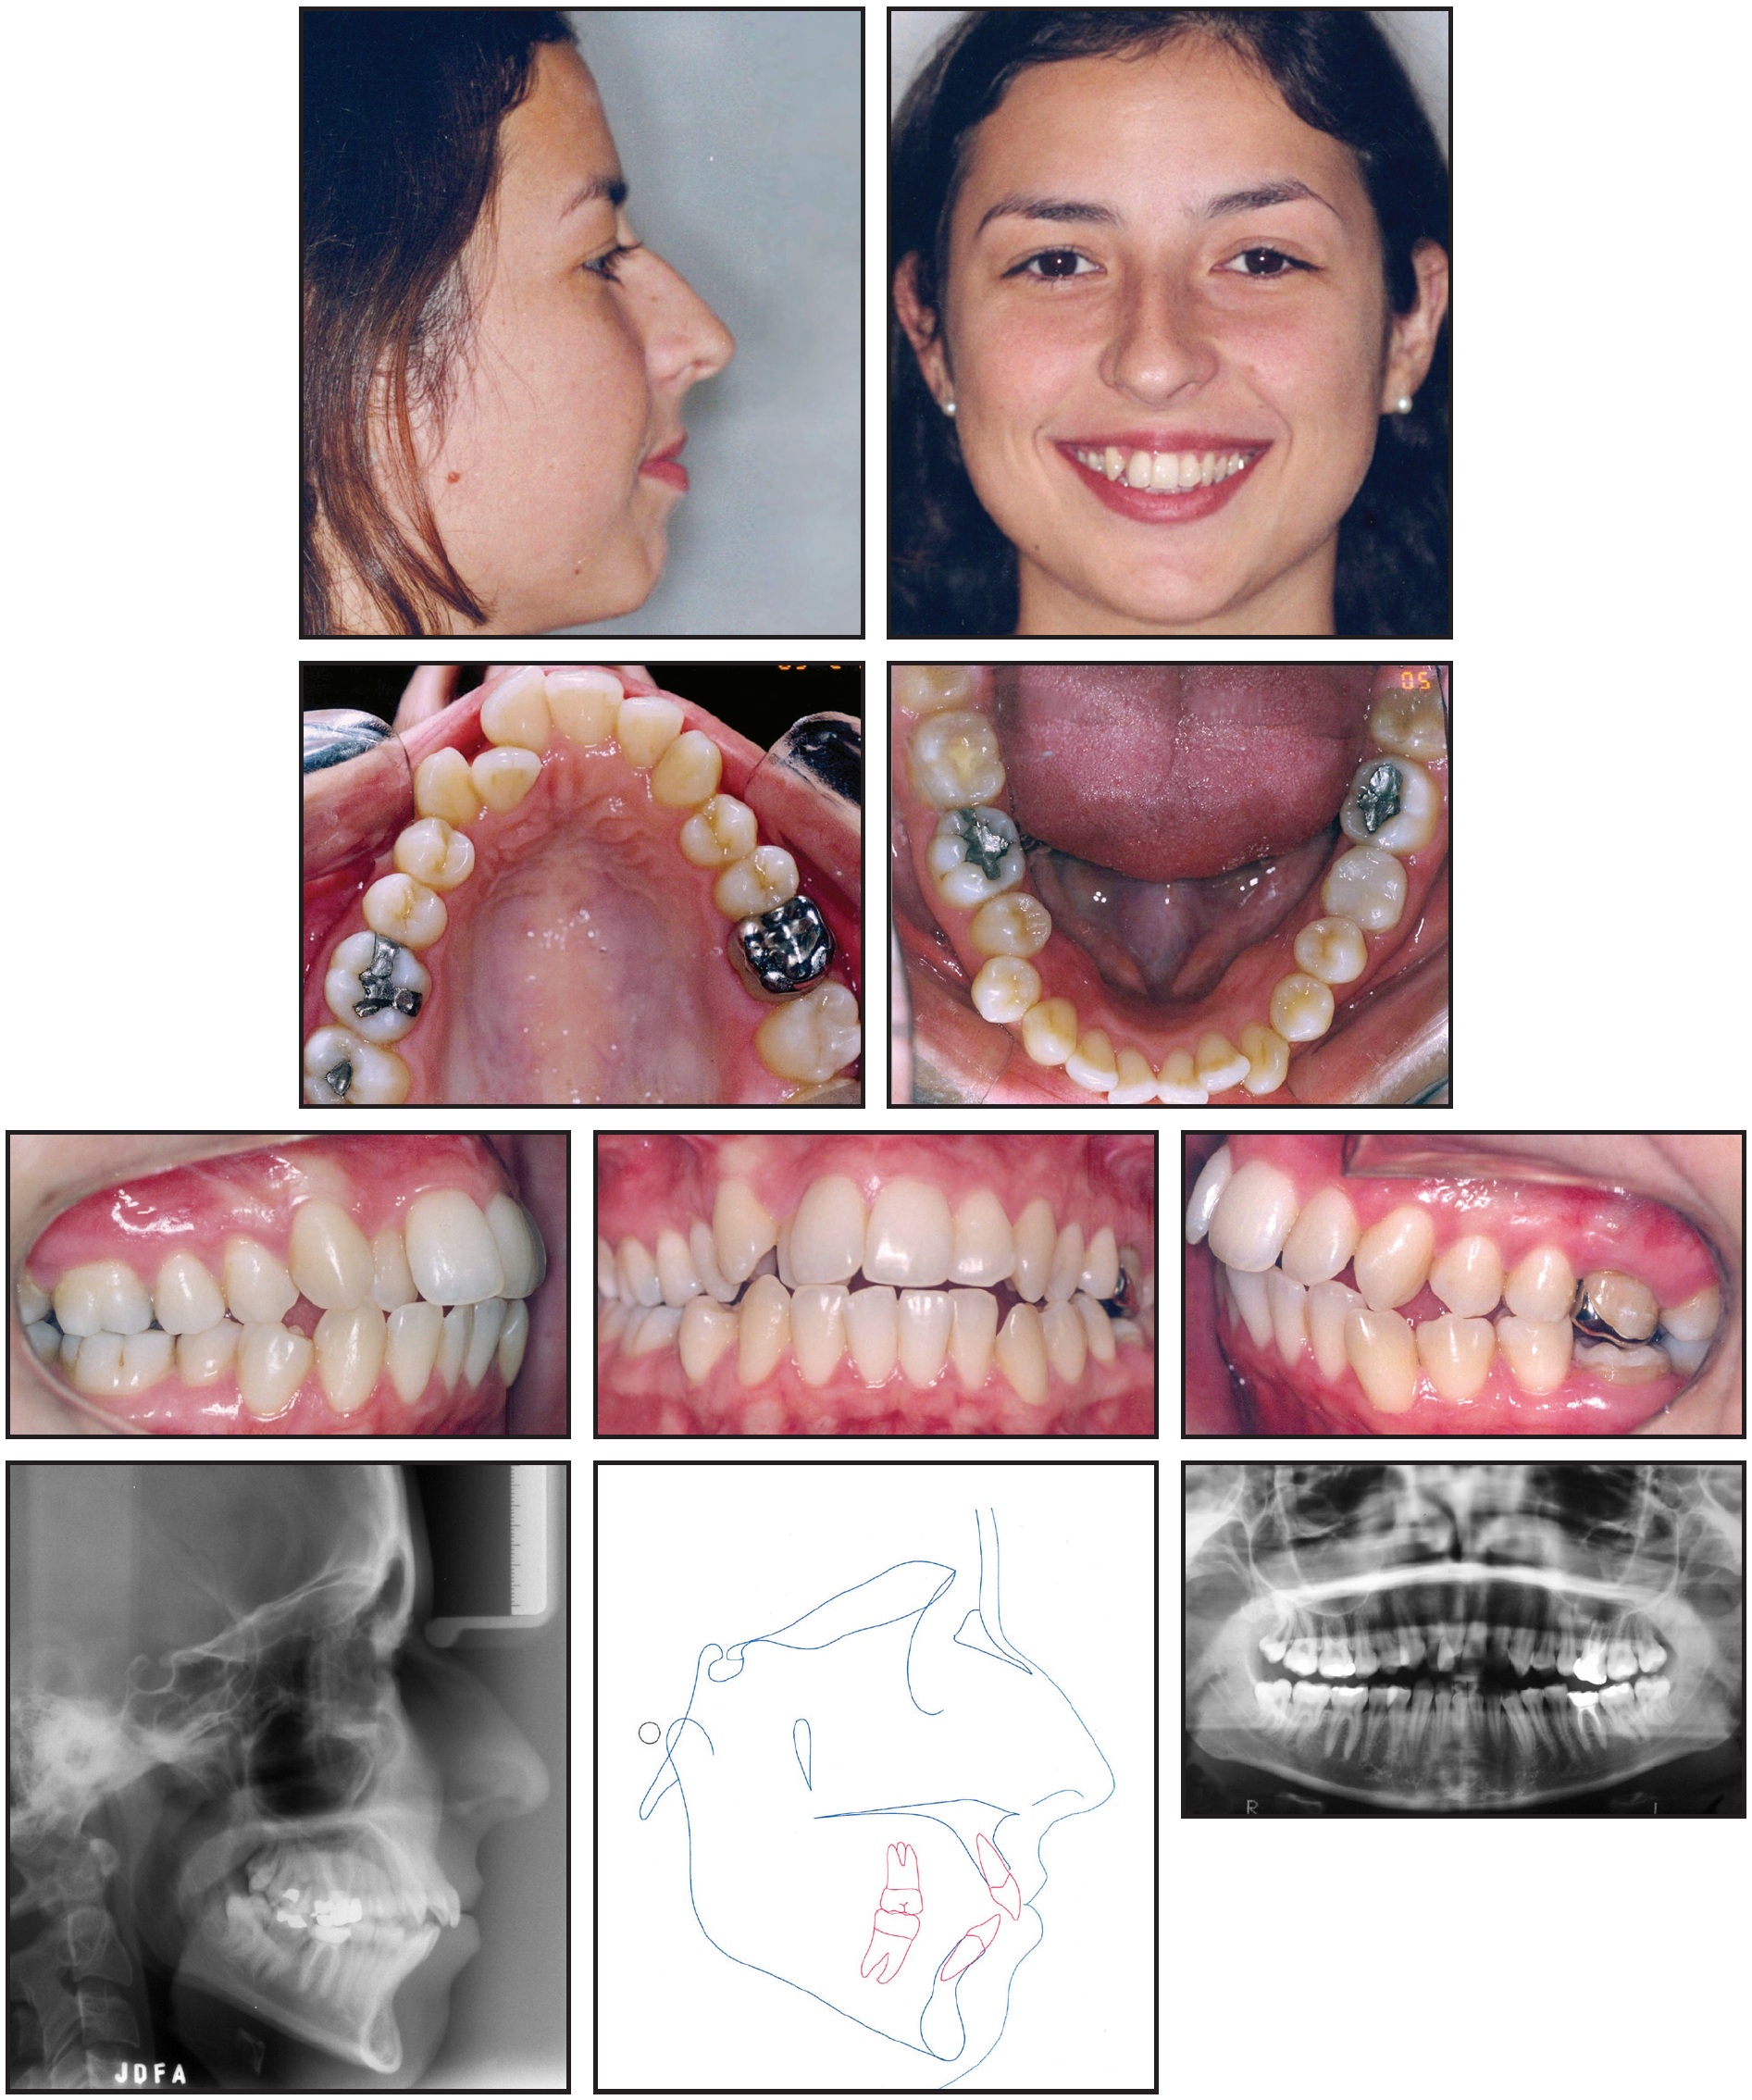

A 22-year-old female presented with the chief complaints of dental crowding, protrusive incisors, and a lack of passive lip seal (Fig. 1).

Fig. 1 22-year-old female patient with Class II, division 1 malocclusion; moderate crowding; protrusive incisors; and 3mm midline deviation before treatment.

The upper anterior region was contracted, the upper right lateral incisor was in crossbite, and moderate crowding was noted. The patient had a 3mm midline deviation to the right, with a dental discrepancy of −8mm in the upper arch and −6.5mm in the lower arch and a Class II, division 1 malocclusion. Extensive crown restorations were present on the upper and lower left first molars; the upper molar needed endodontic retreatment, and the lower one required a full crown restoration.

Cephalometric analysis (Table 1) indicated a skeletal Class II relationship (ANB = 7°; Wits appraisal = +8mm) with protrusive lower incisors (1-NB = 39°; IMPA = 105°) and a vertical growth pattern (GoGn-SN = 38°; FMA = 29°).

Orthodontic treatment goals were to level and align the teeth, reduce the protrusion of both upper and lower incisors, and establish disclusion guidance. The extraction of four teeth (one in each quadrant) would be required to gain enough space. Since the left first molars presented with extensive structural damage and needed endodontic and prosthetic treatment, while the left third molars showed acceptable morphological conditions, the upper and lower left first molars were extracted along with the upper and lower right first premolars.